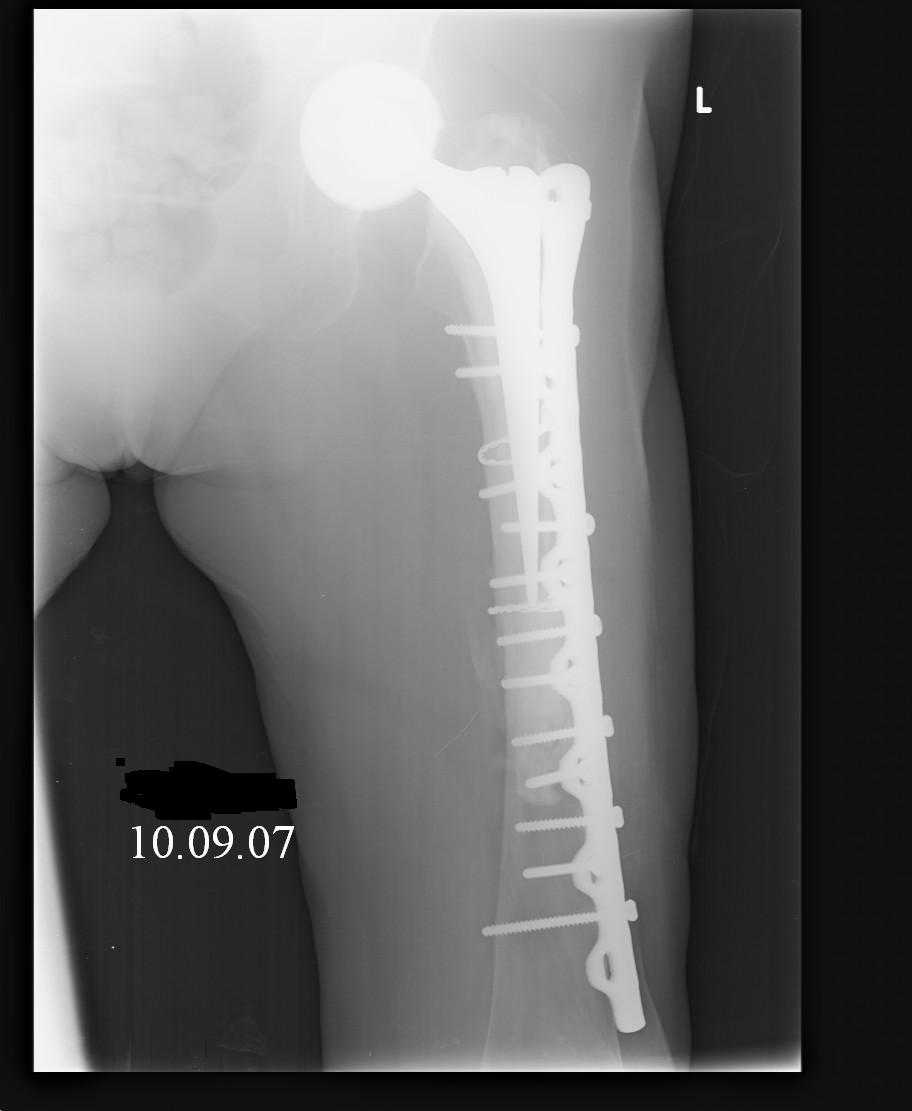

Hello! This is just illustration in one of the choice of treatment